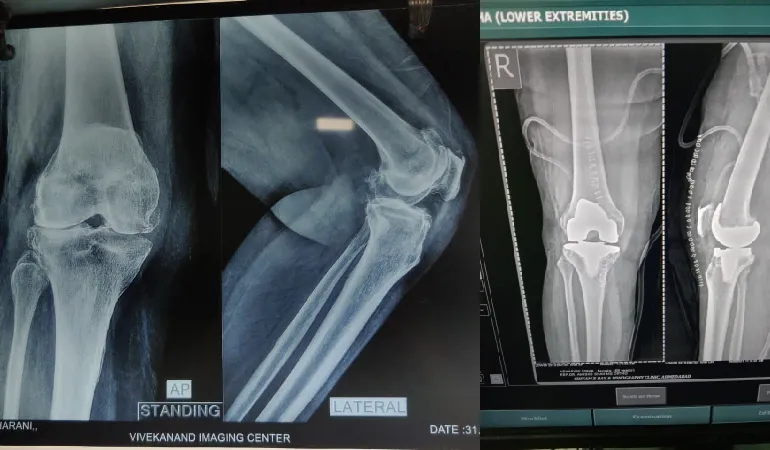

His clinical journey is defined by an extraordinary milestone of performing more than 10,000 successful surgeries. This vast experience ranges from routine fracture care to some of the most complex joint replacements and arthroscopic procedures in the region. Dr. Shah’s practice at Vedant Hospital, Gota, is built on the pillars of precision, ethical practice, and deep-rooted compassion.

PatientI underwent knee replacement surgery both knee five years before and I am feeling good I have no pain in daily activity and I am doing all my work Thank you very much Dr Amish sir is Best knee replacement doctor.

Mahendra Shah